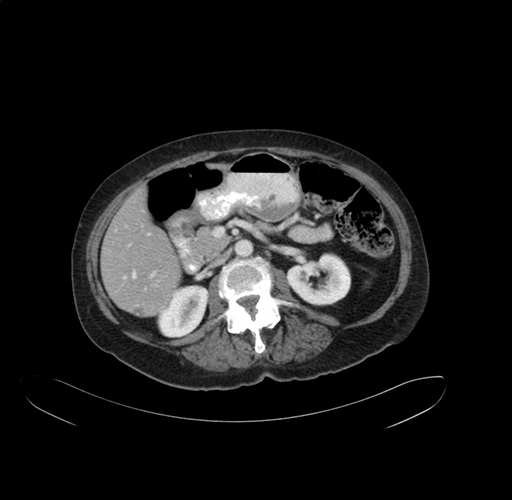

Coronal Venous